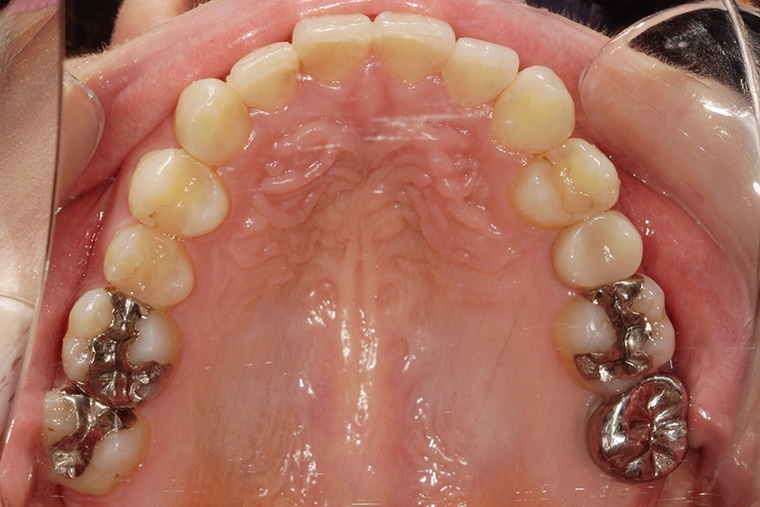

Case Study32歳女性ガタガタな歯のマウスピース矯正-矯正期間6ヶ月(2024年1月開始)